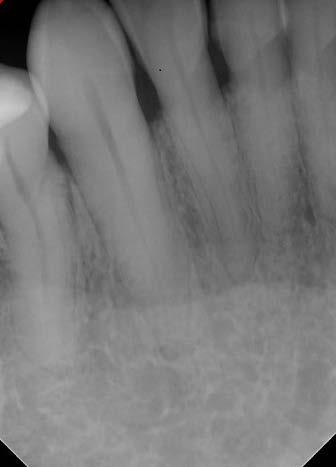

Technique for extracting tooth or root tip from underneath fixed partial denture emphasizes use of magnification from dental loupes or dental surgical operating microscope for precision when performing technique-sensitive procedure. Case report.